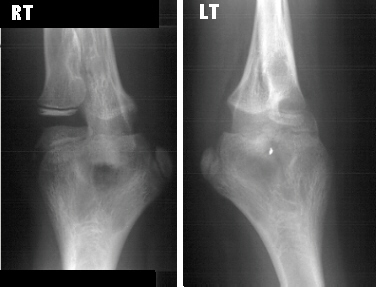

Order of Xray links: 1. Internal Rotation, 2. External Rotation,

3. AP, 4. Lateral.

The patient is an 11 year old, otherwise completely healthy

boy, who presented for evaluation of his left arm. He states he

has always had limited range of motion of his left arm, however,

his mother states that it was not until recently she became concerned.

The patient is right hand dominant. This does not cause him any

functional problems and he has no pain. The mother and boy are

concerned because the right and left arms are different. The left

arm demonstrates a shoulder with full range of motion (ROM) and

strength 5/5. The elbow has a flexion from 0 to 135 degrees, but

the forearm is fixed in 45 degrees of pronation without active

or passive supination. The wrist has full ROM with some hyper-mobility,

especially in radial and ulnar deviation. The strength is 5/5

in elbow flexion/extension, wrist flexion/extension and grip.

He is neurovascularly, intact. The right arm also demonstrates

normal motion at the elbow with flexion from 0-135 degrees but

limited supination from 0-50 degrees and pronation from 0-20 degrees.

The remainder of his exam was normal.

right arm is normal and the left arm has radioulnar synostois.